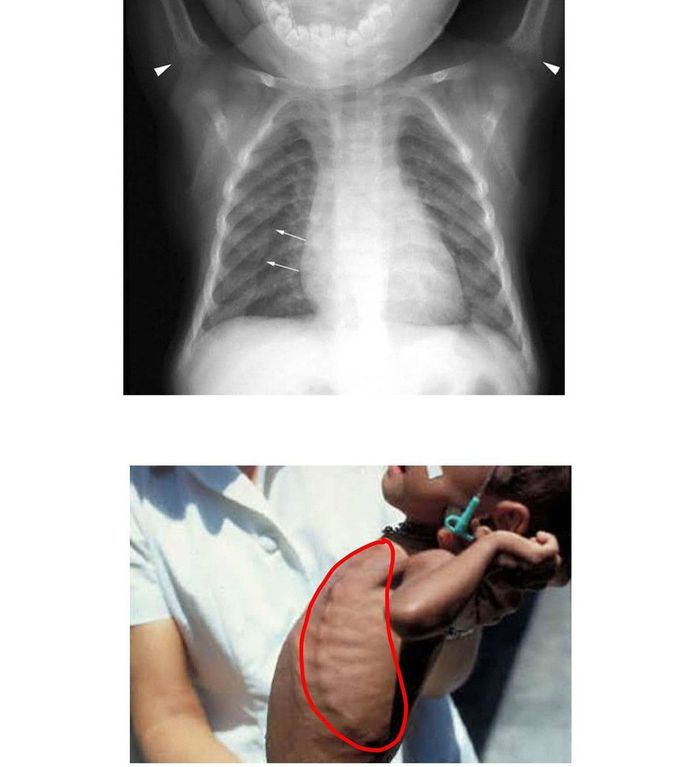

Identify the Sign

What is this sign called?

rachitic rosary , vit d deficiency

Rachitic Rosary - Rickets / x-linked Hypophosphatemia